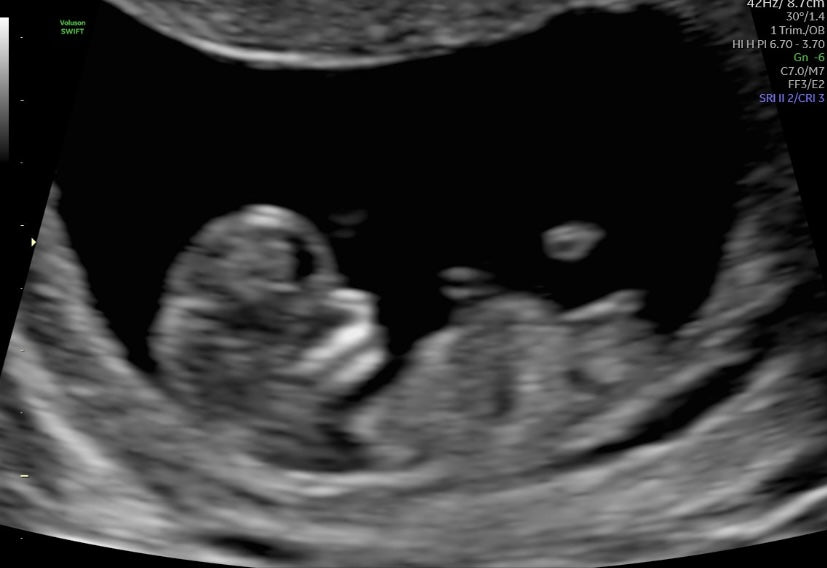

I suffer from a condition called vaginismus which has been extremely difficult to treat and a very hard road. I eventually received surgery years after starting treatment with my doctors and travelled from Scotland to London to have this procedure done - this allowed us to use Mosie Baby. After one cycle of trying with Mosie Baby, I found out I’m pregnant with our miracle and we cannot thank you enough! For anyone that has vaginismus, please remember you aren’t on your own and there light at the end of the tunnel. It took me years but I would do it all again for this moment!